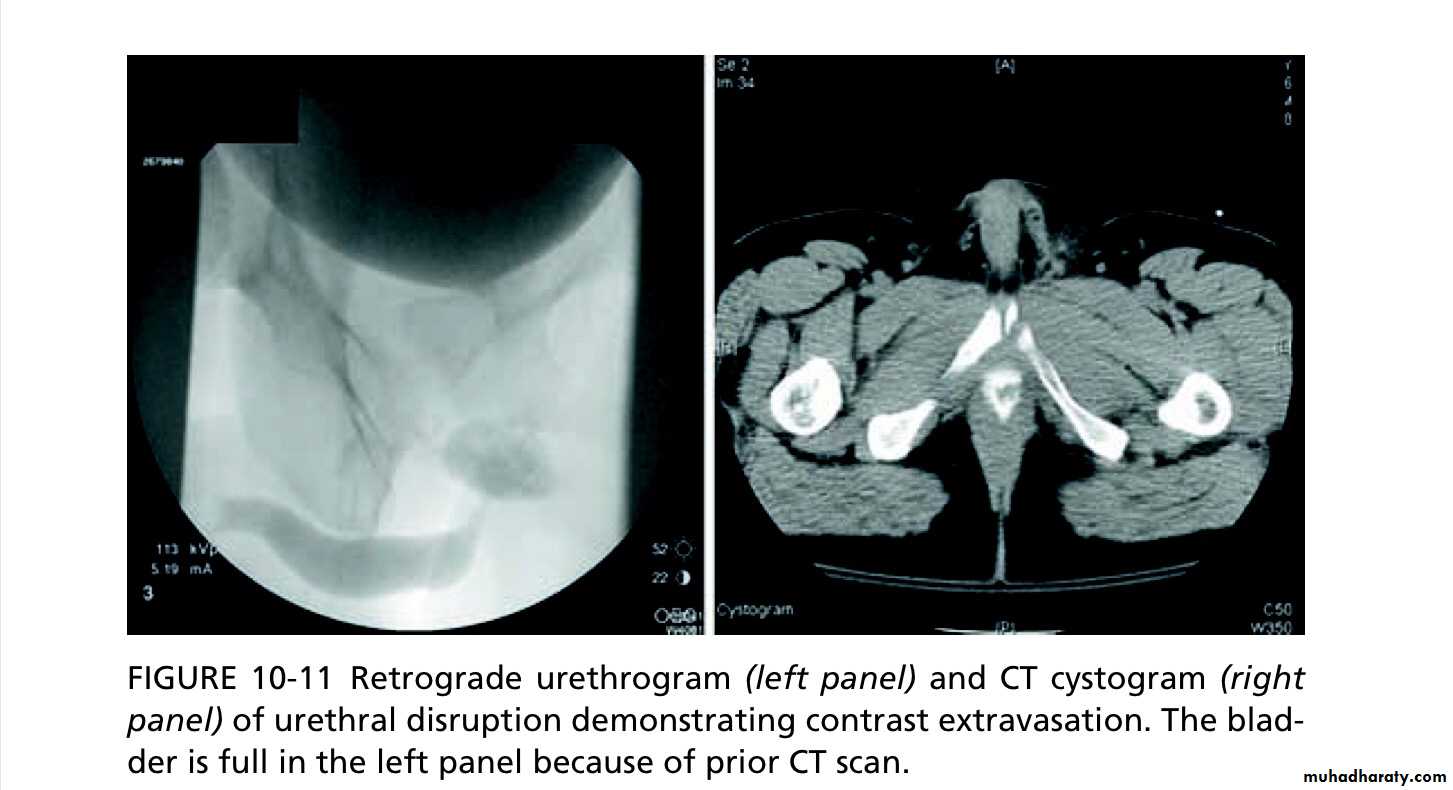

Retrograde urethrogram:

to detect urethral injury. Some hospitals perform retrograde urethrography only when blood is present at the meatus; others do this in all pelvic fracture patients where the pubic rami have been disrupted.

Retrograde urethrography delineates the extent of urethral injury.

3-Complete rupture of anterior urethra Leak of contrast from the urethra on retrograde urethrogram, no filling of the posterior urethra or bladder. The urethra may either be immediately repaired (if a surgeon with sufficient experience is available) or an SPC can be placed with delayed repair.